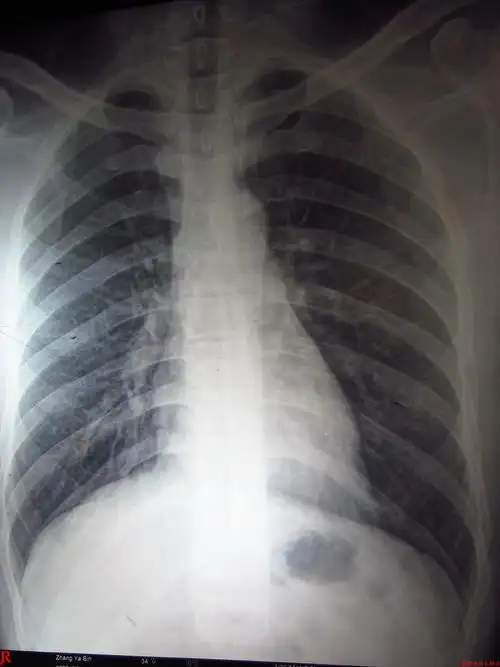

正常肺x片

这张胸片肺部有问题吗?